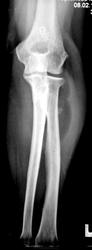

Пациентка направлена на рентгенографию костей предплечья.

Мягкотканное муфтообразное образование в/3 предплечья, с костями предплечья не связанное. Вызывает сомнение плотноинтенсивное округлое включение в мягких тканях по луче-ладонной поверхности на уровне верхней трети лучевой кости.

Мое мнение, судя по распространению мягкотканного образования от суставной капсулы локтевого сустава - синовиома. Относительно плотноинтенсивного включения ответить затрудняюсь.

У пациентки хорошо видимое опухолевидной образование, безболезненное. Пациентка отмечает, что данное образование заметила около 4- лет тому назад, и которое в последние два года значительно увеличилось в размерах. Жалобы у пациентки чисто косметического характера.